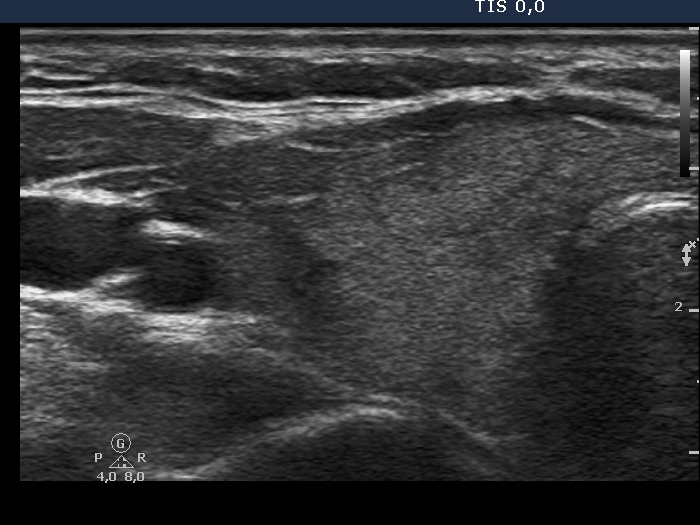

The echogenicity of the nodule - case 755 (ultrasonographic picture 2)

Right lobe, longitudinal view. There is a small hypoechogenic area in the upper and an echonormal lesion in the central part of the thyroid.